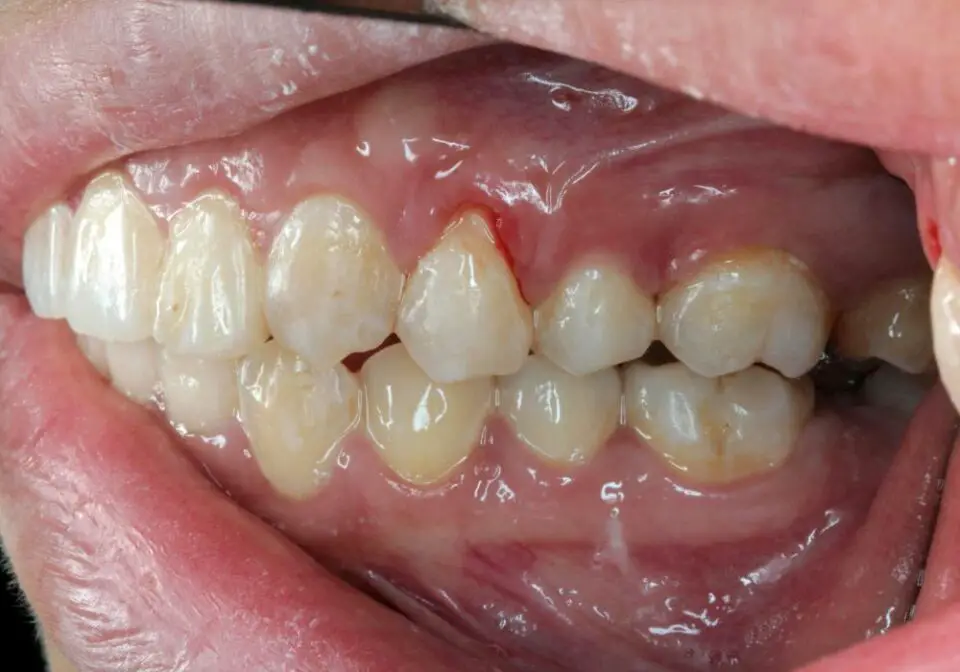

GUM RECESSION SURGERY Connective Tissue Graft Dr. Allen